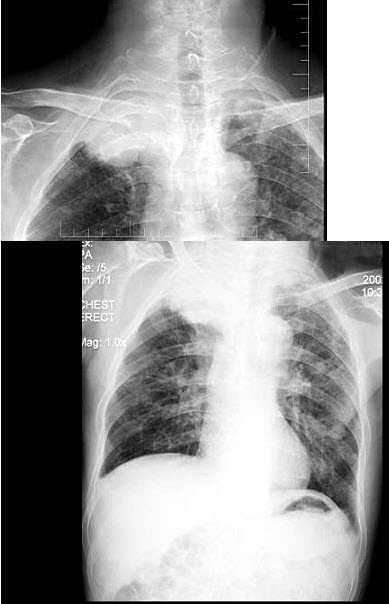

B.提高清晰度

男,56岁,劳累后心慌气促10余年,近来自觉症状加重。临床听诊,心尖区有舒张期和收缩期杂音,行胸部X检查,如图所示,描述正确的是()

A.后前位示双房影,左心缘第三弓突出

B.右前斜位示左心房增大,心后上缘后突压迫服钡食管

C.左前斜位示心影向后下方突出

D.考虑三尖瓣狭窄

E.考虑二尖瓣狭窄并关闭不全